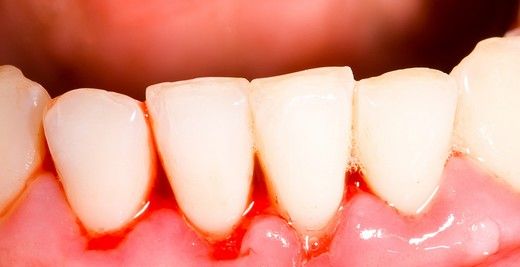

Diş Kanaması Orucu Bozar mı?